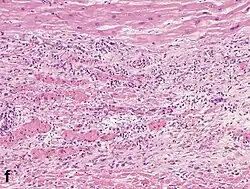

Under the microscope, myocardial infarction presents as a circumscribed area of ischemic, coagulative necrosis (cell death). On gross examination, the infarct is not identifiable within the first 12 hours.[22]

Although earlier changes can be discerned using electron microscopy, one of the earliest changes under a normal microscope are so-called wavy fibers.[23] Subsequently, the myocyte cytoplasm becomes more eosinophilic (pink) and the cells lose their transversal striations, with typical changes and eventually loss of the cell nucleus.[24] The interstitium at the margin of the infarcted area is initially infiltrated with neutrophils, then with lymphocytes and macrophages, who phagocytose ("eat") the myocyte debris. The necrotic area is surrounded and progressively invaded by granulation tissue, which will replace the infarct with a fibrous (collagenous) scar (which are typical steps in wound healing). The interstitial space (the space between cells outside of blood vessels) may be infiltrated with red blood cells.[22]

These features can be recognized in cases where the perfusion was not restored; reperfused infarcts can have other hallmarks, such as contraction band necrosis.[25]